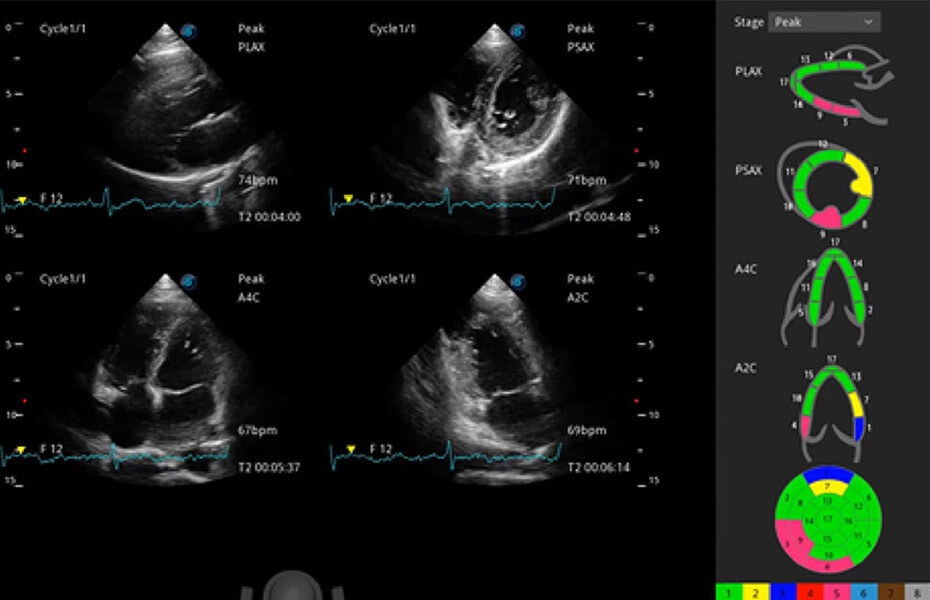

ProPet 60 作為一款高端臺(tái)式動(dòng)物超聲設(shè)備,為動(dòng)物醫(yī)生的日常診斷提供了一系列貼合動(dòng)物臨床需求、解決臨床實(shí)際問(wèn)題的高級(jí)成像功能。憑借全系列高清探頭,滿足醫(yī)生對(duì)腹部、心臟、生殖、淺表、肌骨等成像的所有需求,切實(shí)幫助您提升檢查效率,提高診斷信心。